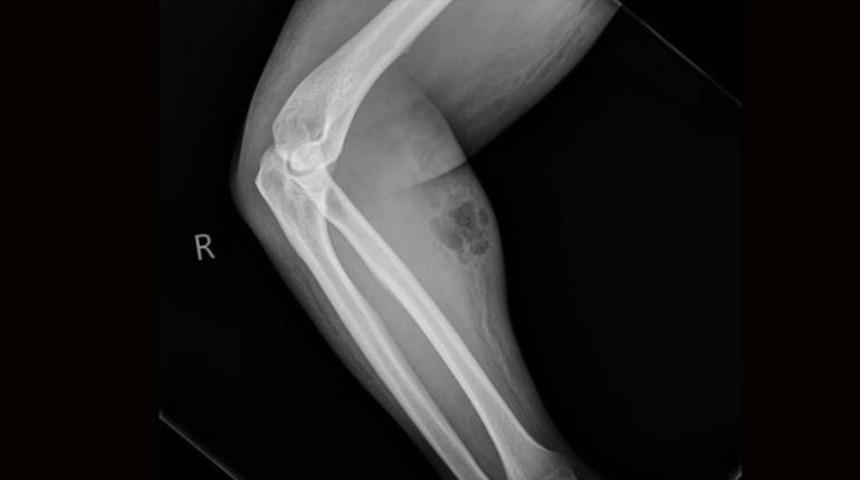

Doktorlar, hastanın ön kolunda ciddi şekilde şişlik ve kızarıklık olduğunu fark etti.

Yapılan tetkiklerde hastanın sırt ağrısını geçireceği düşüncesiyle 18 ay boyunca koluna kendi spermini enjekte ettiği ve deri altı yangısı rahatsızlığına yakalandığı ortaya çıktı.

İnternetten satın aldığı enjeksiyon iğnesi ile 18 ay boyunca ön koluna ayda bir doz sperm enjekte eden ve bu sayede sırt ağrılarından kurtulacağına inanan hastanın sırt ağrıları dinmek bilmedi.